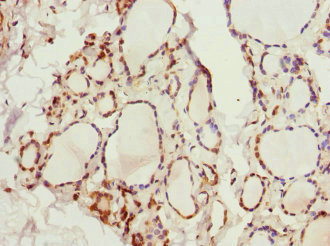

Immunohistochemistry of paraffin-embedded human thyroid tissue using CSB-PA012008DSR1HU at dilution of 1:100